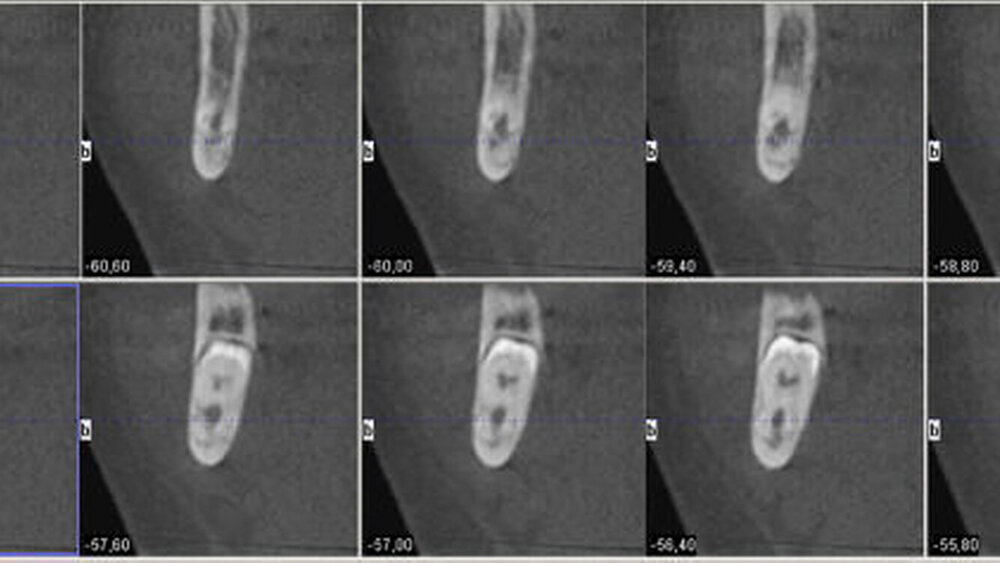

Aufgrund der engen Lagebeziehung der Weisheitszähne zum Nervus alveolaris der jeweiligen Seite wurde zur weiterführenden Diagnostik eine digitale Volumentomografie durchgeführt.

In der 3-D-Aufnahme bestätigte sich der Verdacht, dass der Nerv zwischen den Wurzeln hindurch zog, wobei beim Zahn 48 die Wurzeln den Nerv komplett umklammerten (Abbildungen 3 und 4). Nach Inzision auf dem aufsteigenden Unterkieferast mit Entlastung an den Zähnen 37 beziehungsweise 47 wurden der Knochen und im Weiteren die Weisheitszähne dargestellt. Die Kronen wurden von der Wurzel getrennt, die Wurzeln separiert und sukzessive entfernt, wobei die Integrität der Nerven auf beiden Seiten erhalten blieb (Abbildung 5).

Eine Verletzung des Nervus alveolaris inferior bei Weisheitszahnentfernung findet sich überproportional häufig in Fällen, in denen auf der Panoramaschichtaufnahme Zeichen zu erkennen sind, wie eine Veränderung des Verlaufes des Nervus alveolaris inferior (Abbildungen 1 und 2), bei überlagerungsbedingter erhöhter Transluzenz im Bereich der Überprojektion von Wurzel und Nerv und bei Unterbrechung der kortikalen Begrenzung des Nervkanals [Blaeser et al., 2003]. Alle diese Kriterien lagen im vorliegenden Fall vor. In der weiterführenden digitalen Volumentomografie ist zu erkennen, wie der Nerv zwischen den Wurzeln liegend hindurchzieht.

Man kann den Nerv-Verlauf im DVT besser beurteilen als in der Panoramaschichtaufnahme.